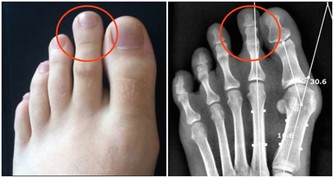

腎貯藏精氣,為人體生殖、造血、生長發育、防衛病邪的基礎物質,平衡身體水液代謝,與膀胱合作排泄尿液,負責納氣,協調呼吸運動,主骨生髓,養腦益智,促進頭髮生長,腎氣通耳,控制聽力,控制二陰的開合。

1、護好雙腳:足部保暖是養腎的一種方法,每天用熱水泡泡腳,在做一些簡單的按摩,睡覺時不要將雙腳正對空調或電扇,不要赤腳在潮濕的地方長期行走。